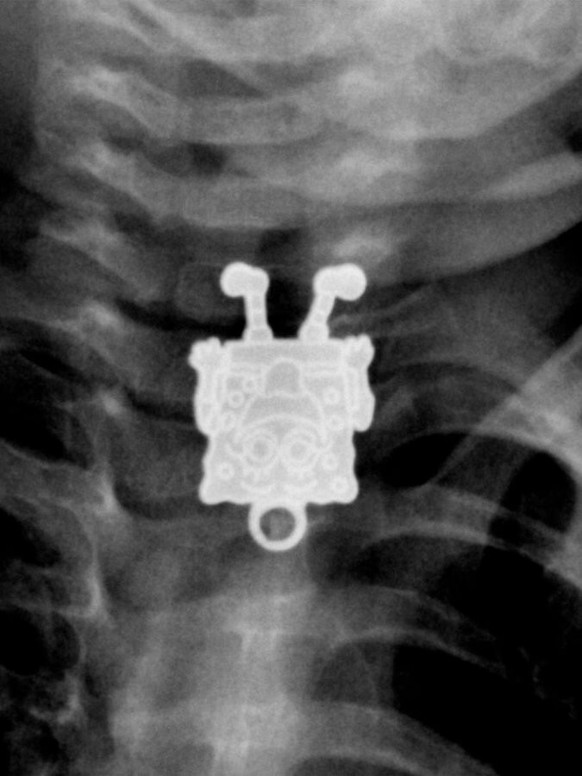

Bob l'éponge?😳